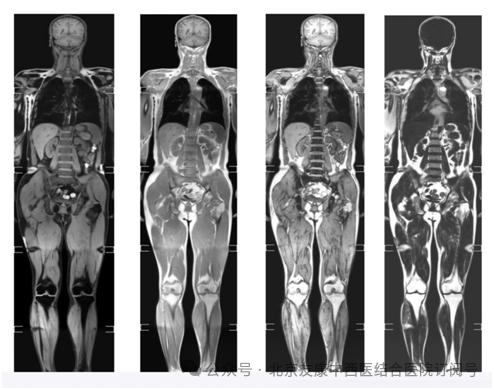

传统PET检查虽有效,但其辐射问题让人望而却步。现在,有了MR类PET,一切变得不同!它如同一位敏锐的健康侦探,能在肿瘤萌芽阶段就精准定位,无论是隐匿的早期病变还是潜在的转移病灶,都逃不过它的“火眼金睛”。

1、零辐射:无X线、无放射性药物,老人、孕妇、儿童都能放心做!PET-CT检查有辐射,正常成年人一年做1-2次,孕妇、儿童等特殊人群要求更严格,MR类PET则全年可重复检查。

3、舒适便捷:一次扫描30分钟左右,相对于传统PET-CT时间更短,且无需检查前准备,躺着即可完成全身检查,无创无痛。

类PET是医学磁共振成像的一项最新技术。2004年,由日本学者首先提出“类PET”概念。之后,全球各大医学研究机构与影像设备生产厂家积极研究,相继推出了可实现“类PET”的成像技术,并很快用于临床。类PET的实质是体部弥散加权成像,又称“背景抑制的全身扩散加权成像(DWIBS)”,是最前沿的磁共振技术。该技术能够一次性全身大范围扫描,在抑制肌肉、脂肪、肝脏等组织背景信号的基础上,突出了病变的显示,大大提高了病变组织尤其是恶性肿瘤及其转移灶的检出率,从而获得全身肿瘤筛查、良恶性肿瘤的鉴别、肿瘤TNM分期及疗效随诊等诊断信息,其成像效果和临床意义与PET有相同的效果,故被称为类PET。